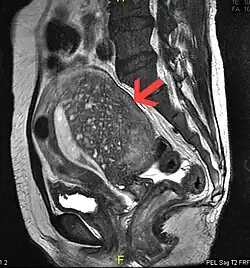

Sagittal MRI of a woman's pelvis showing a uterus with adenomyosis in the posterior wall. Gross enlargement of the posterior wall is noted, with many foci of hyperintensity.

Magnetic resonance imaging

Magnetic resonance imaging (MRI) provides slightly better diagnostic capability compared to TVUS, due to the increased ability of MRI to differentiate objectively between different types of soft tissue.[24] This is possible with MRI's higher spatial and contrast resolution. Overall, it is estimated that MRI has a sensitivity of 74% and specificity of 91% for the detection of adenomyosis.[11] Diagnosis through MRI focuses predominately upon investigating the junctional zone. The uterus will have a thickened junctional zone with darker/diminished signal on both T1 and T2 weighted sequences.[24]

Three objective measures of the junctional zone can be used to diagnose adenomyosis.[24]

1. A thickness of the junctional zone greater than 8–12 mm. Less than 8 mm is normal.

2. A junctional zone width being greater than 40% of the width of the myometrium.

3. Variability in the width of the junctional zone being greater than 5 mm.

Interspersed within the thickened, darker signal of the junctional zone, one will often see foci of hyperintensity (bright spots) on the T2 weighted scans representing small cystically dilatated glands or more acute sites of microhemorrhage.[24]

MRI is limited by other factors, but not by calcified uterine fibroids (as is ultrasound). In particular, MRI is better able to differentiate adenomyosis from multiple small uterine fibroids.